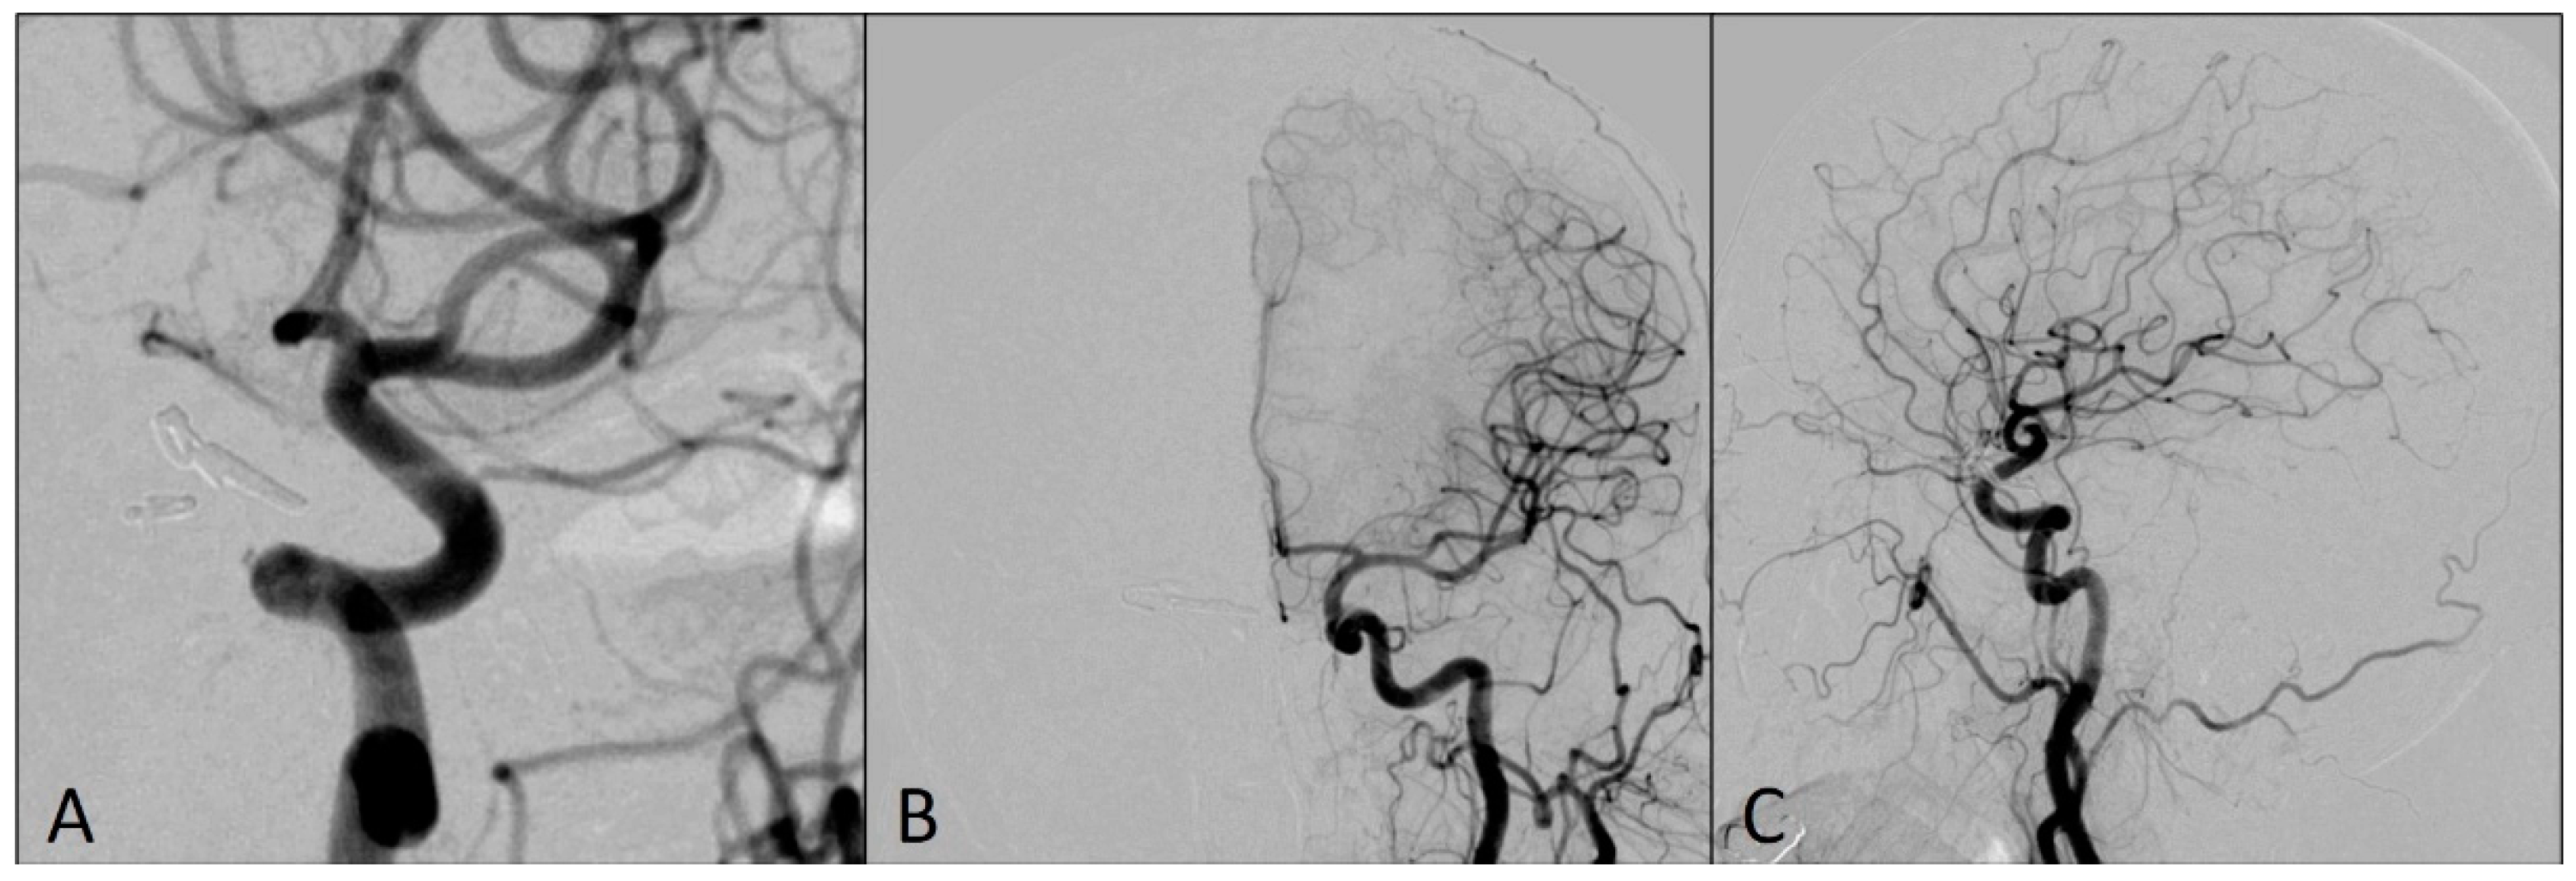

2. Case Report